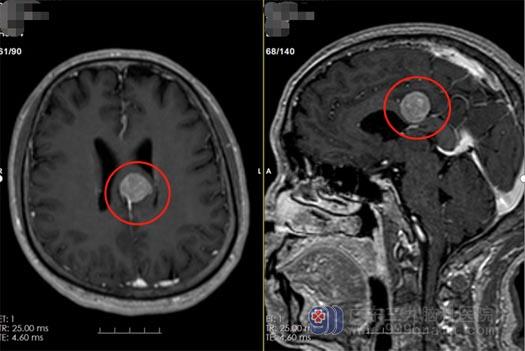

▲术前

一年前,区叔因为经常有头痛去当地医院检查,结果发现颅内长了个小脑膜瘤。医生告知肿瘤是良性的,区叔的条件完全可以考虑早点切除。一听要开颅切除,吓得他赶紧跑回了家。没有听医生的建议,他反而自我安慰:“肿瘤是良性的,良性的就没关系”。

今年2月,区叔头痛越发严重,而且还出现手不自主抖动,复查发现肿瘤比原来长大了,一家人这才意识到事情的严重。经朋友介绍联系了广东三九脑科医院鲁明副院长。